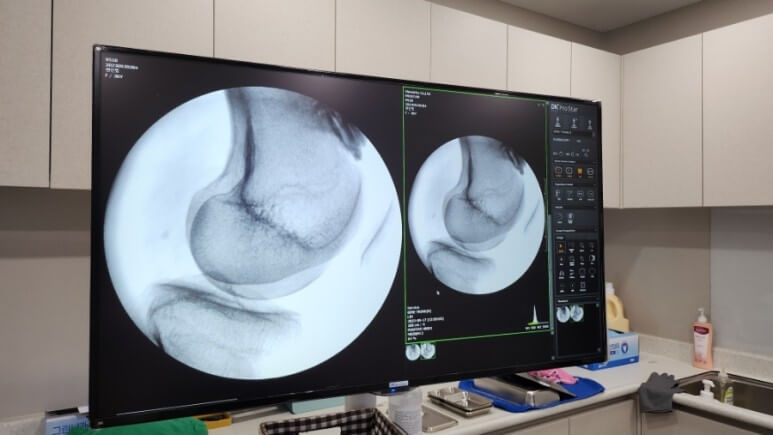

첫 진료 보고 엑스레이 찍음. 근데 다시 진료 볼때 난 엑스레이 못봄;;;

엑스레이 상에 오른쪽 무릎에 석회가 있다고 설명들었는데

못봐서 좀 아쉬웠다?...